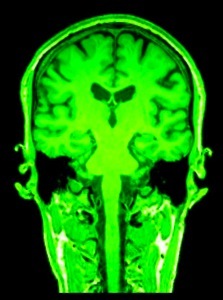

plan coronal

ou frontal

plan coronal

ou frontal